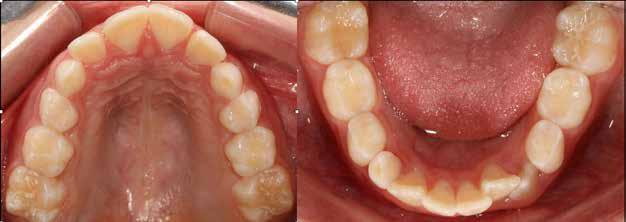

A fogszabályozás aktív fázisa után minden kezelésnél a retenció, a passzív helyben tartó fázis a kezelési eredmény megtartására rendkívül fontos!

Az Essix retainerek, az egy fogívre kiterjedő mélyhúzott sínek, valamint a felső és alsó frontfogakra orálisan ragasztott fix retainerek mellett, a harapás sagittális rögzítésében elengedhetetlen szerepe van az ún. Pitts Izom Tréning Splint-nek, amelybe a páciens élharapásban összeharap, így az megakadályozza az alsó fogsor visszamozdulását a disztálharapásos helyzetbe (13. kép)